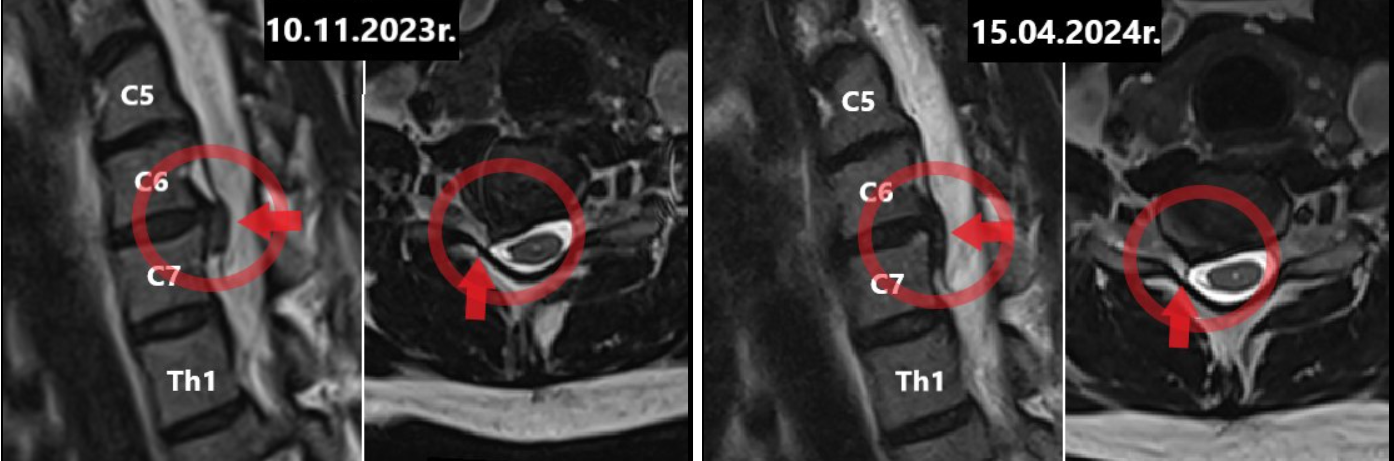

Wcześniejsze badanie rezonansem magnetycznym z 10.11.2023 wykazało wyraźną przepuklinę dysku między C6-C7, powodującą podrażnienie korzenia nerwowego. Pacjentce wyznaczono termin operacji na czerwiec 2024.

Po 6 tygodniach ból całkowicie ustąpił.                                                                                                                                                                  A teraz najlepsze – pacjentka wykonała kontrolne badanie MRI 15 kwietnia 2024 roku.

Wynik? Przepuklina między C6–C7 uległa znacznemu wchłonięciu. Lekarz który miał przeprowadzić operację był zdumiony efektem – operacja została odwołana ze względu na brak bólu oraz cofnięcie się zmian.

Obraz MRI jasno pokazuje: to ta sama pacjentka, ten sam poziom C6-C7, a przepuklina znacząco się cofnęła.